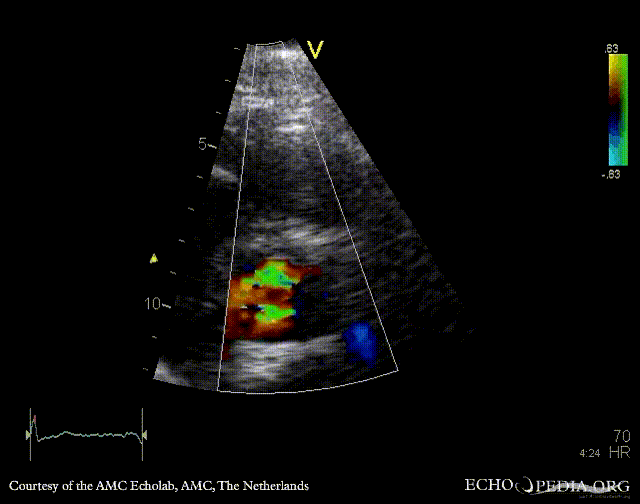

Endocarditis of aortic valve

PLAX: Color Doppler, moderate aortic regurgitation PSAX